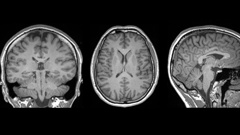

Brain injury breakthrough: NZ scientists discover telltale marker after concussion

Thursday, 27 March 2025, 7:33amMore than 33,000 cases of mild traumatic brain injury are reported in New Zealand each year – a third of them from sport...